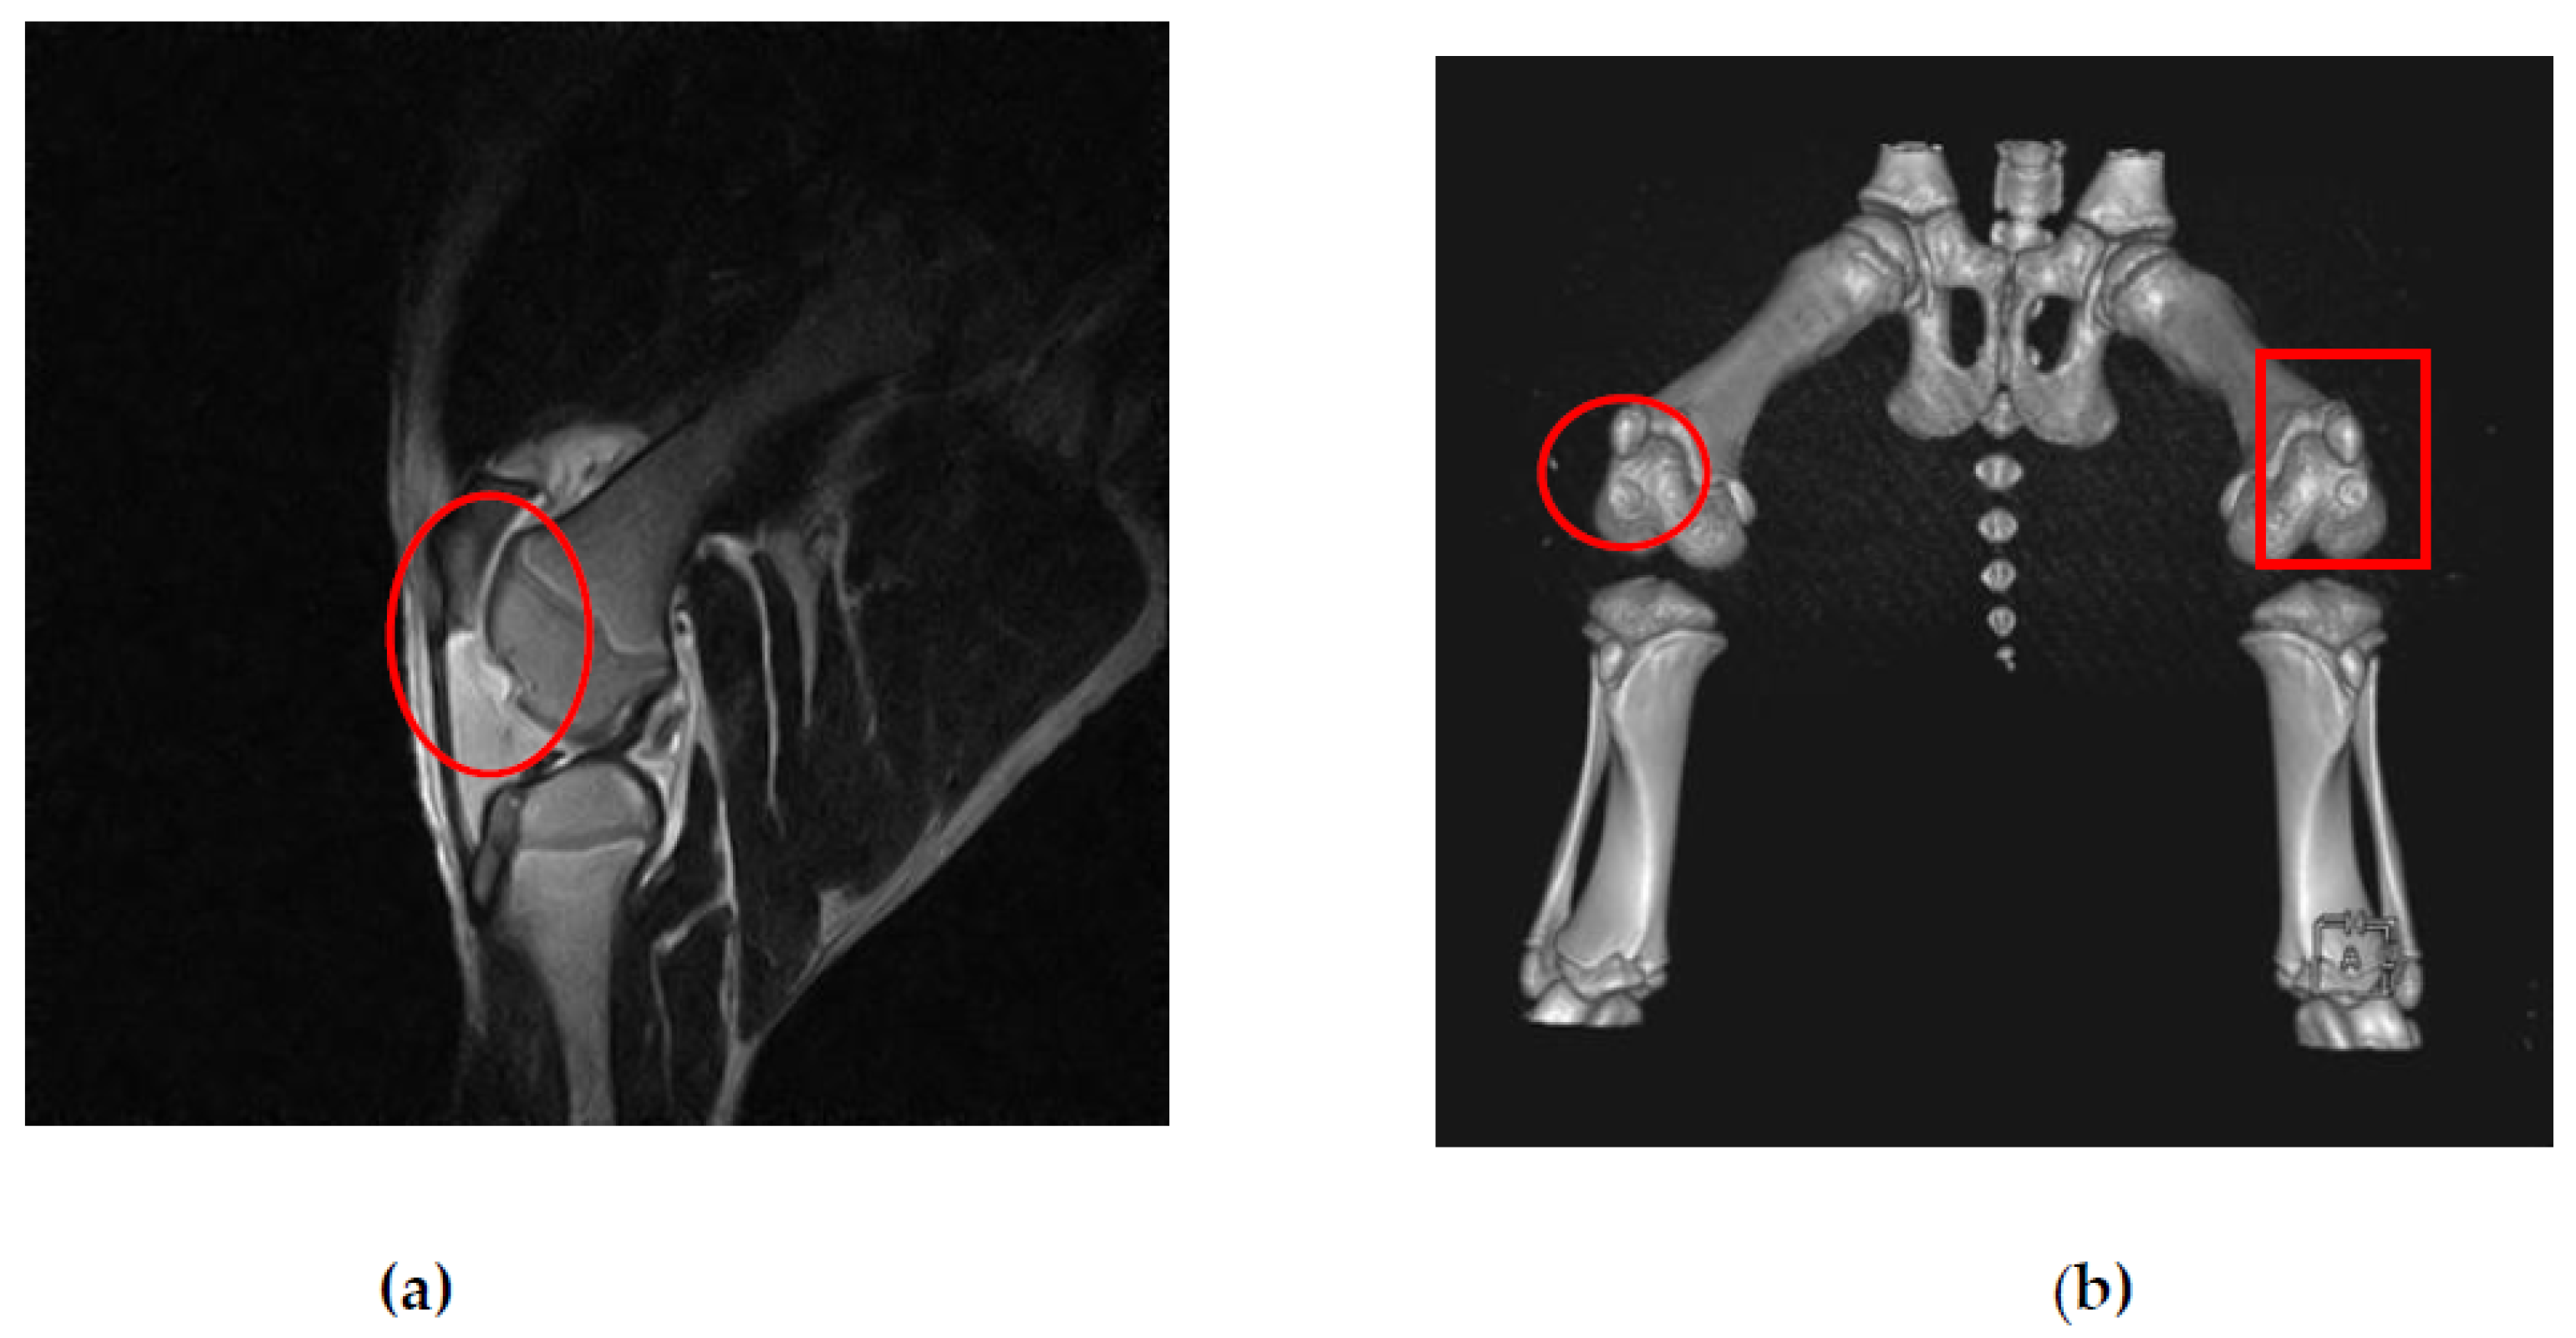

3.1. MRI and CT Observations